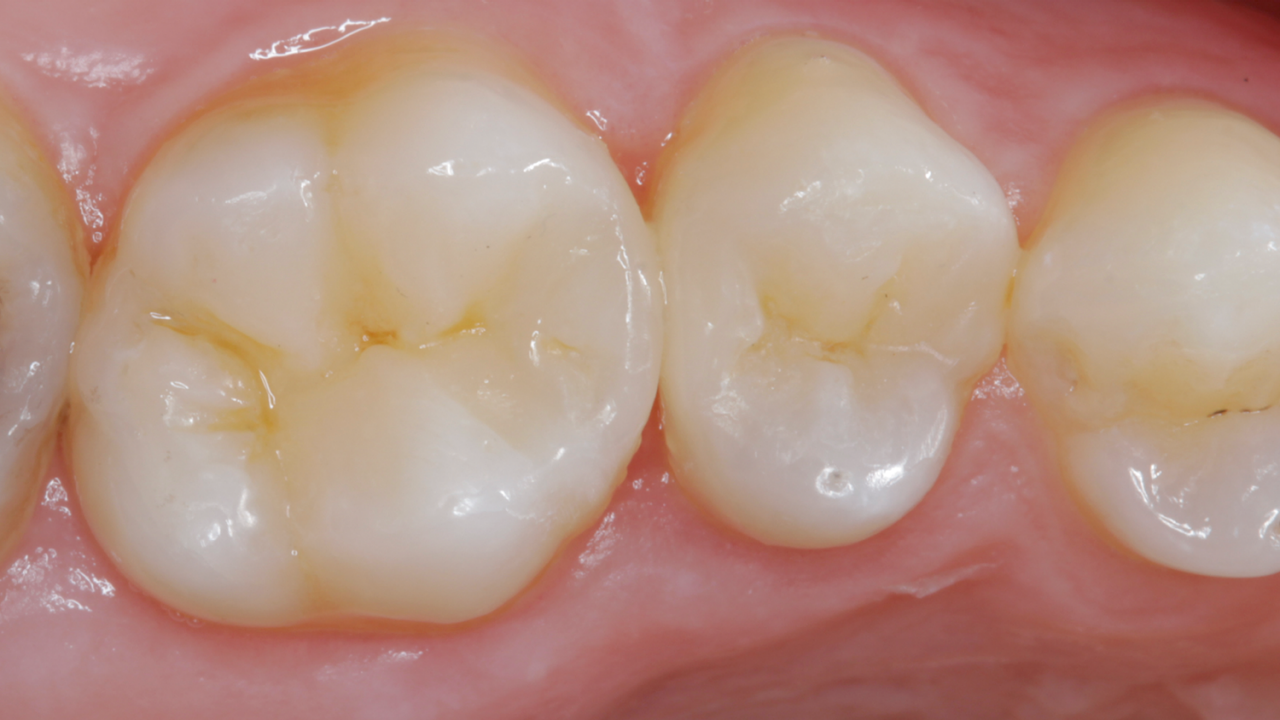

Excellence in class II layering composite

Results: 3-month recall. Occlusal-palatal view depicting excellent gloss retention. Note the characterization and natural appearance obtained with Ceram.x Spectra ST universal composite A2 and BW.